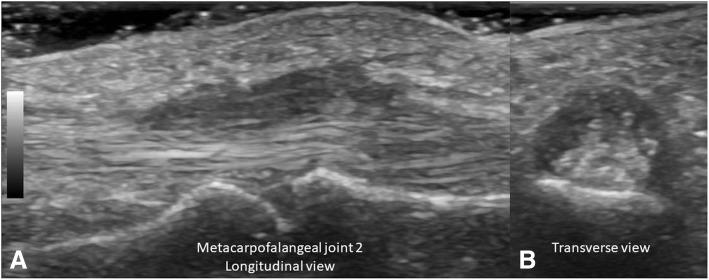

Musculoskeletal Ultrasonography (MSUS) is an important tool for the clinical assessment in Juvenile Idiopathic Arthritis (JIA). The objective of this study was to evaluate the reliability of MSUS to detect elementary lesions: synovitis, tenosynovitis, cartilage damage and bone erosions in the wrist and metacarpal (MCP) joints of patients with JIA.

Thirty children in various subgroups of JIA according to ILAR criteria, were included in this cross-sectional study. Clinical data including painful, swollen and limited joints were recorded. Five rheumatologist ultrasonographers, blinded to the clinical evaluation, evaluated the presence of elementary lesions in the wrist and MCP 2 and 3 joints bilaterally. The synovitis was graded in B-Mode and Power Doppler (PD). In addition to descriptive statistics intra- and inter-observer reliability was calculated using Cohen's kappa according to Landis and Koch.

US detected more synovitis than the clinical examination (62% vs 28%, 30% vs 23% and 22% vs 17% in the wrist, second and third MCP joints respectively). The intra-observer concordance for synovitis in all joints was excellent in B-Mode (k 0.84 .63-1.0 p = 0.001), except for MCP 2, where it was good (0.61, IC 95% .34-89, p = 0.001). For both modalities (PD, B-Mode) tenosynovitis, cartilage damage and bone erosions it was also excellent. Regarding synovitis grading the concordance was excellent for all grades (0.83-1.0, IC 95% 0.51.1.0, p = 0.001), except for grade 1 where it was good (0.61, IC 95% 0.43-.83, p = 0.001). Reliability inter-observer for grayscale synovitis (0.67-0.95, IC 95% 0.67-1.0, p = 0.001), tenosynovitis grayscale (0.89, IC 95% 0.78-0.99, p.001), damage cartilage (0.89, IC 95% 0.78-0.99, p = 0.001), PD (0.66, IC 95% 0.39-1.0, p = 0.001). The concordance for grading synovitis was excellent, but for grayscale grade 1 and 2 (.66, IC 95% .53-.74, p = 0.007) and PD grade 1 and 2 (0.63, IC 95% .58-.91, p = 004) was good.

The intra- and inter-observer reliability of MSUS for inflammatory and structural lesions is good to excellent for the wrist and MCP in patients with JIA.